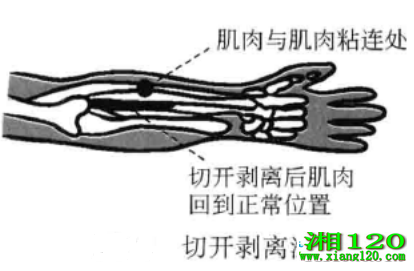

4、切开剥离法

当几种软组织互相粘连结瘢,如肌肉与韧带、韧带与韧带互相结报粘连时,将刀口线沿肌肉或韧带走向平行剌入,将相互间的粘连或瘢痕切开。